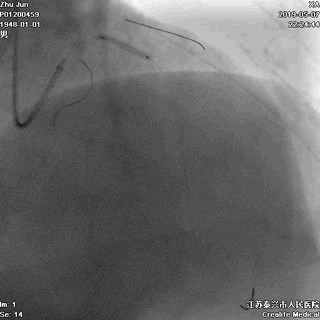

导丝分别进回旋支和前降支

LAD和LCX,任一根血管都不能丢!这一步的价值,就相当于是构筑生命线。